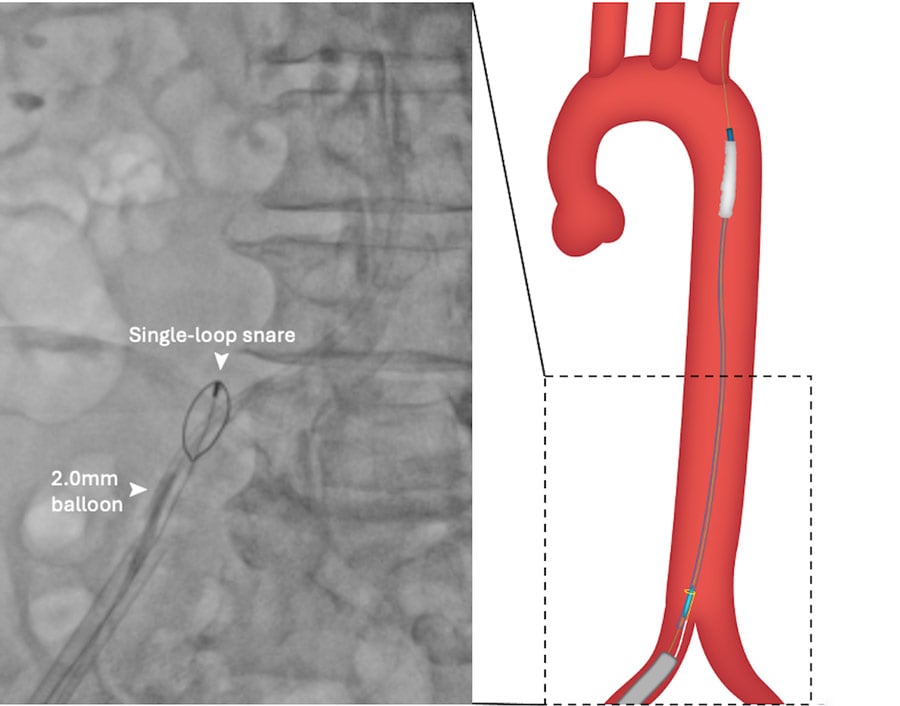

With a new 0.035’ wire running parallel to the internalised balloon, a 20F sheath was introduced. However, the angle for balloon retrieval remained very unfavorable due to femoral calcification and tortuosity. To straighten the system, A Gaia Next® 2 wire (Asahi Intecc, Aichi, Japan) was used to rewire the central lumen of the transected balloon shaft in a ‘tip-in’ fashion (Figure 1D, Moving image 2).

Figure 1D: ‘Tip-in’ rewiring of central lumen of transected valvuloplasty balloon.

Once this was achieved, internal anchoring with a 2-mm balloon inflated within the wire lumen of the transected valvuloplasty balloon and ipsilateral snaring with a 5-mm Amplatz Goose SnareTM (Medtronic) straightened the system and allowed successful retrieval of the balloon (Figure 1E, Figure 1F, Moving image 3).

Figure 1E: Ipsilateral snaring and 2-mm balloon anchoring in central lumen of transected balloon.